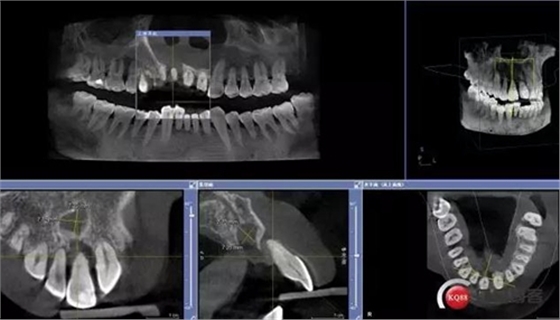

患者:王XX 年齡:42 上前牙松動數(shù)年,從未做過任何處理,今來院就診;檢查:CBCT示上前牙區(qū)顎側(cè)一大小約7x7mm囊腫;治療計劃:即刻種植同期摘除囊腫

術前CBCT